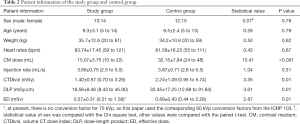

In the present study, 27 cases were eventually enrolled in the study group, and the average age was 9.3±3.1 years. There were 5 cases with the abnormal origin of the coronary artery, 3 cases with slightly thinner coronary diameter, 1 case with coronary sinus dilatation, 1 case with myocardial bridge, and 17 cases were normal. For the 27 cases in the control group, the average age was 9.5±2.4 years. There were 5 cases with the abnormal origin of the coronary artery, 1 case with coronary sinus dilatation, and 21 cases were normal. The contrast medium dose was 15.07±3.58 mL, and the ED was 0.57±0.31 mSv in the study group, which were 53% and 36% lower than the contrast medium dose (32.15±7.84 mL) and ED (0.89±0.43 mSv) in the control group, respectively (P<0.05). The injection rate was 3.66±0.75 mL/s in the study group and 3.87±0.71 mL/s in the control group (P>0.05). Other information is listed in Table 2.

Full table